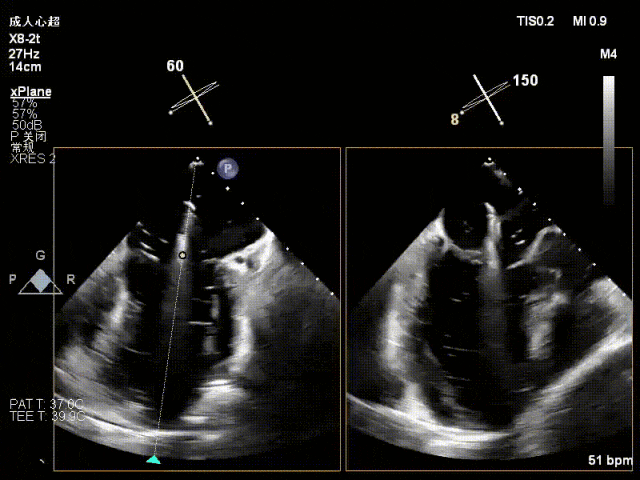

术中超声要点

术前术后对比图

术前

术后

术后,出院检查报告显示夹子位置固定,二尖瓣、三尖瓣及主动脉轻微反流,左房增大,左室内径正常上限,EF值正常下限(WMSI 1分)。